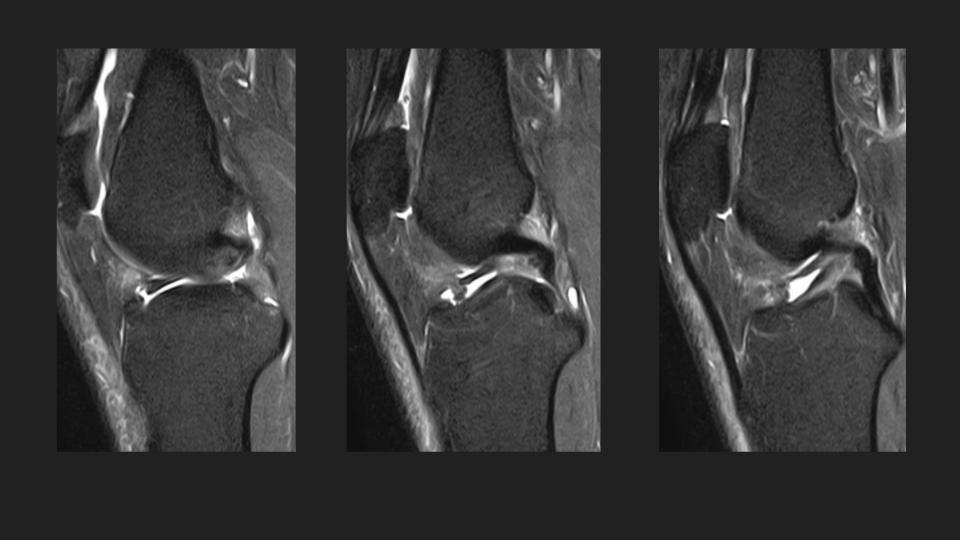

27M knee pain

This is an anteromedial meniscofemoral ligament. It looks alot like the relatively common ligamentum mucosum, but is is rare (approx 0.4% incidence) and inserts onto the central aspect of the anterior horn medial meniscus rather than the patella. It is eye-catching, but incidental and should not be resected. Reference article.

meniscofemoral ligament ( RID2806 )